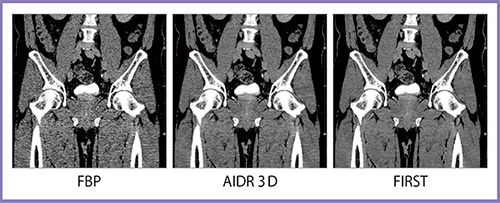

股関節CTは,FBPと比べるとAIDR 3Dでも大幅にノイズが低減されているが,FIRSTではさらにノイズが低減され,骨梁構造も描出できている(図7)。また,ストリークアーチファクトが強く出やすい肩口の頸椎CTでも,FIRSTではアーチファクトが抑制できている(図8)。

図7 股関節CT